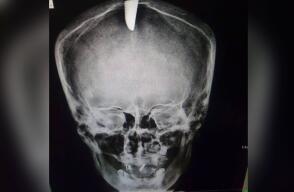

¡Increíble! Sobrevivió hombre que tenía un CUCHILLO en la cabeza

La víctima de 55 años fue agredido por dos sujetos en la localidad de Bosa.